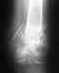

Без рентгенограмм невозможно уяснить, какое повреждение было, и и что имеется на сейчас. "Укусы пчел" - это не лечение ни при какой ситуации. Если есть деформация - устранить ее можно только хирургически. Что конкретно нужно делать - по смутному рассказу про неизвестно какой "перелом голеностопа" предложить невозможно. Можно показать снимки здесь, можно приехать на консультацию очно (Московская, 12, с собой паспорт, полис и все справки-снимки, относящиеся к делу).